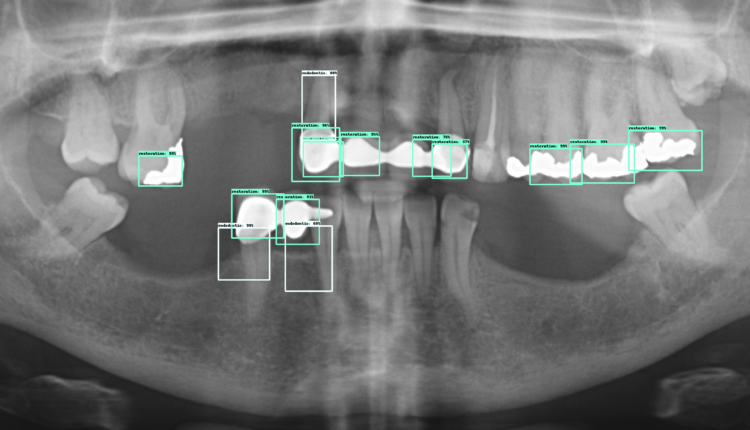

How do I know what type of dental implant I have?